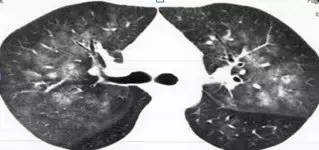

1. 肺泡蛋白沉积症

患者的肺像铺路石一样

2. 马赛克灌注(Mosaic perfusion)

这是肺内通气灌注不一致的表现,主要是小支气管炎症导致肺内局部积气,像马赛克拼图一样

4. 肺淋巴管平滑肌肌瘤病

弥漫性的 GGO

5. 肺外伤